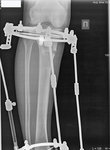

Рентген в 56 дней.

Сращение идёт отлично!